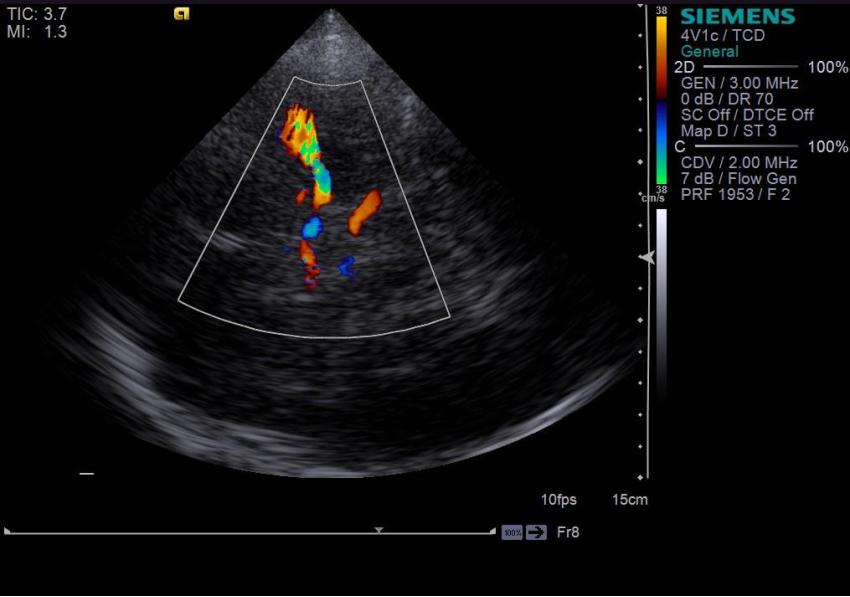

The examination is performed with a sector transducer through 'cranial windows', as these are the areas where bones of the skull are thinner and allow the best transmission of ultrasound. On the side of device, a good penetrating ability is provided by a stream of waves with low frequency. Since the higher the frequency, the faster the ultrasound wave attenuates, it is best to use transducers with a frequency of 1-6 MHz.

However, in order to obtain a diagnostically-appropriate image, one sensor with the appropriate frequency is not enough. You also need a machine with a good power which allows us to obtain an image with acceptable 2D resolution and high color Doppler sensitivity. We all know that machines are divided into different classes. In this article, we want to show you that for a good head vascular examination, it is not necessary to choose a premium class machine with an exorbitant price.

Along with this line, we can safely put Siemens Acuson S2000/3000; s2000/3000 Helx and Helx Evolution, where the imaging between these models will not differ significantly. Also in terms of power and quality, Medison WS/RS80 and HS70/60; Aloka Arietta V70/60; Aloka Arietta V70/60.